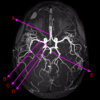

Which arteries do the arrows point to? [1]

Lenticulostiate arteries